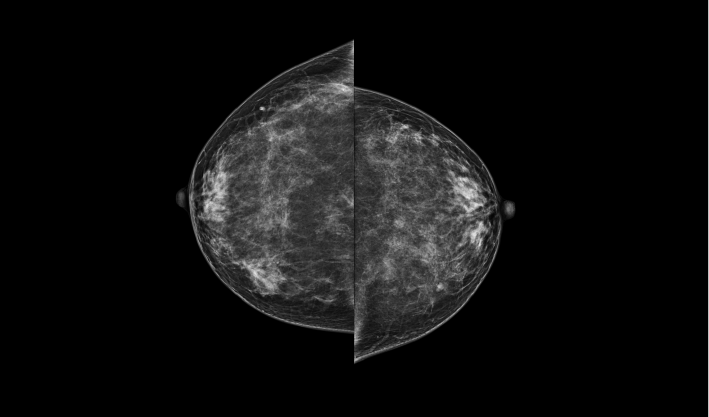

头尾位(CC位) 内外斜位(MLO位) 补充体位(根据需求)

一键式视图切换